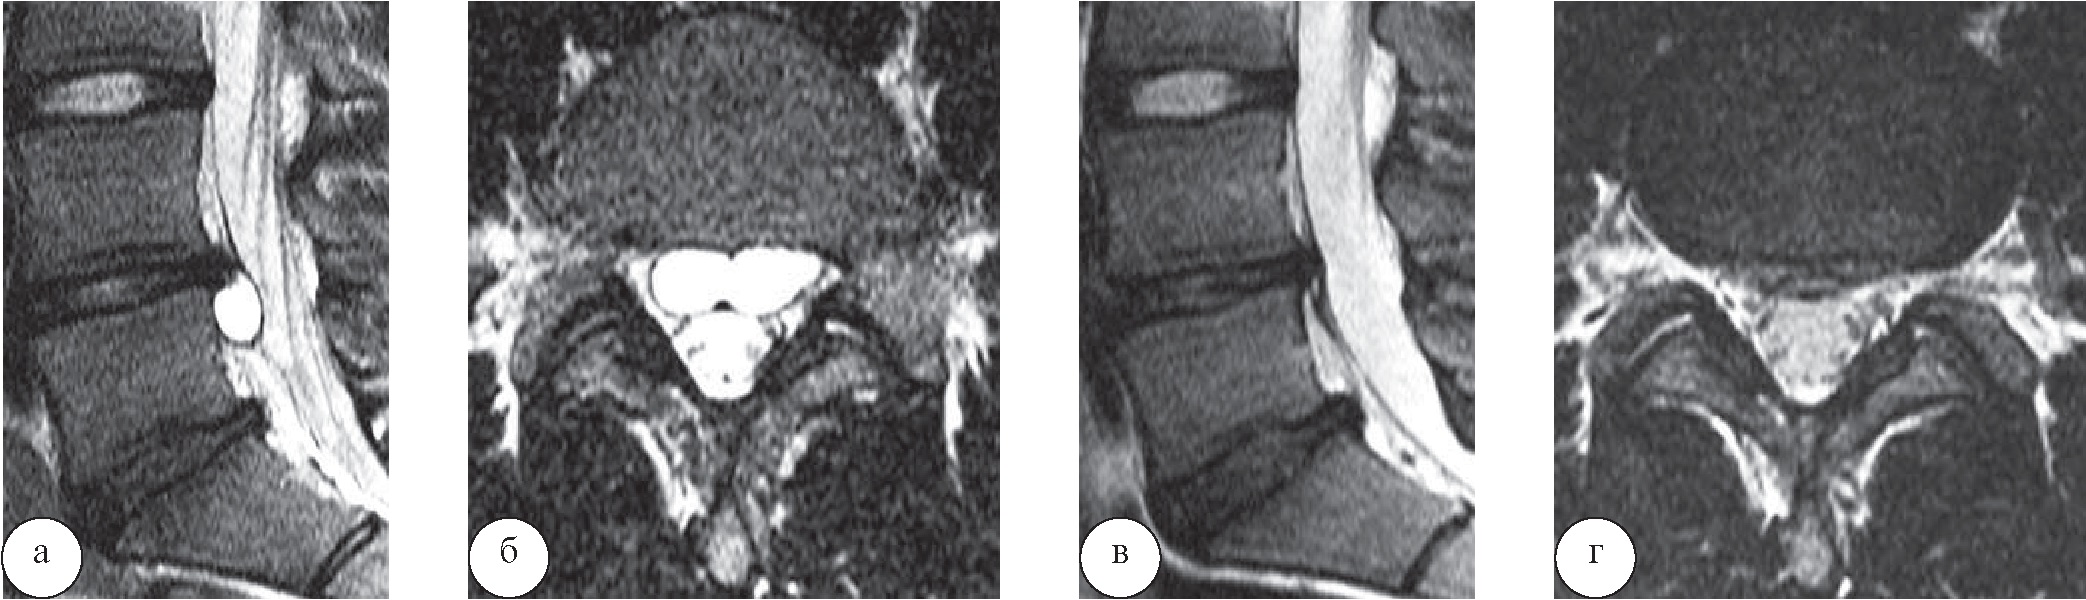

и нестероидными противовоспалительными препаратами, ограничивалась нагрузка на поясничный отдел позвоночника. У одного больного на фоне проводимой терапии в течение 2 месяцев произошел регресс болевого синдрома. По данным контрольной МРТ, через 7 месяцев отмечена резорбция дисковой кисты (рис. 1).

Рис. 1. Спонтанная резорбция кисты межпозвонкового диска LIV–LV у пациента Ф., 20 лет: а, б – сагиттальная и аксиальная проекции МРТ в режиме Т2-ВИ (05.05.2016 г.); в, г – те же проекции МРТ (05.12.2016 г.)